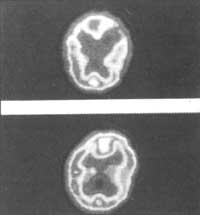

Herrialde industrializatutan 65 urtetik gorako populazioaren %10 dementziak jota dago. Adibidez, herrialde horietan 8 milioi lagunek Alzheimer-en eritasun ezaguna jasaten dute. CERETEC izeneko produktu berri bati esker diagnostikatzea posible izango da. Molekula hau erradioaktiboki markatuta egonik, organismoarentzat kaltegabea da eta pazientean injektatua izan ondoren zenbait orduz garuneko zeluletan finkatzen da.

Gero eskaner edo EMNz garunaren irudiak har daitezke eta garun-morfologia, garunaren funtzionamendua hain zuzen ere, ikusi ere bai. Teknika honek dementzi mota desberdinak diagnostikatzeaz at, garunean egon daitezkeen arazo baskularrak detektatzen lagun dezake